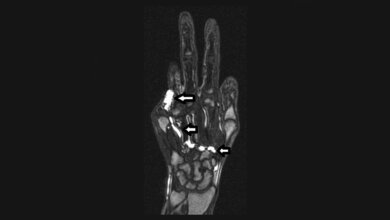

Gefäßerkrankungen stellen eine bedeutende Herausforderung für die moderne Medizin dar und erfordern fortschrittliche diagnostische Ansätze. Dieser Artikel beleuchtet die Rolle moderner Bildgebungsverfahren, darunter CT, MRT, Angiografie, Phlebografie und Sonografie, in der Diagnostik und Therapieplanung. Besondere Schwerpunkte liegen auf Protokolloptimierung, Kontrastmittelmanagement und interdisziplinärer Zusammenarbeit. Herausforderungen wie Kontrastmittelreaktionen und die Untersuchung akuter Gefäßverletzungen werden diskutiert. Zukünftige Entwicklungen wie KI und spektrale Bildgebung werden ebenfalls thematisiert, um die diagnostische Präzision und Patientensicherheit weiter zu verbessern.

Vascular diseases pose a significant challenge in modern medicine, requiring advanced diagnostic approaches. This article highlights the role of modern imaging techniques, including CT, MRI, angiography, phlebography, and ultrasound, in diagnostics and therapy planning. Special emphasis is placed on protocol optimization, contrast agent management, and interdisciplinary collaboration. Challenges such as contrast agent reactions and acute vascular injury assessment are discussed. Future advancements, such as AI and spectral imaging, are also addressed to further enhance diagnostic precision and patient safety.